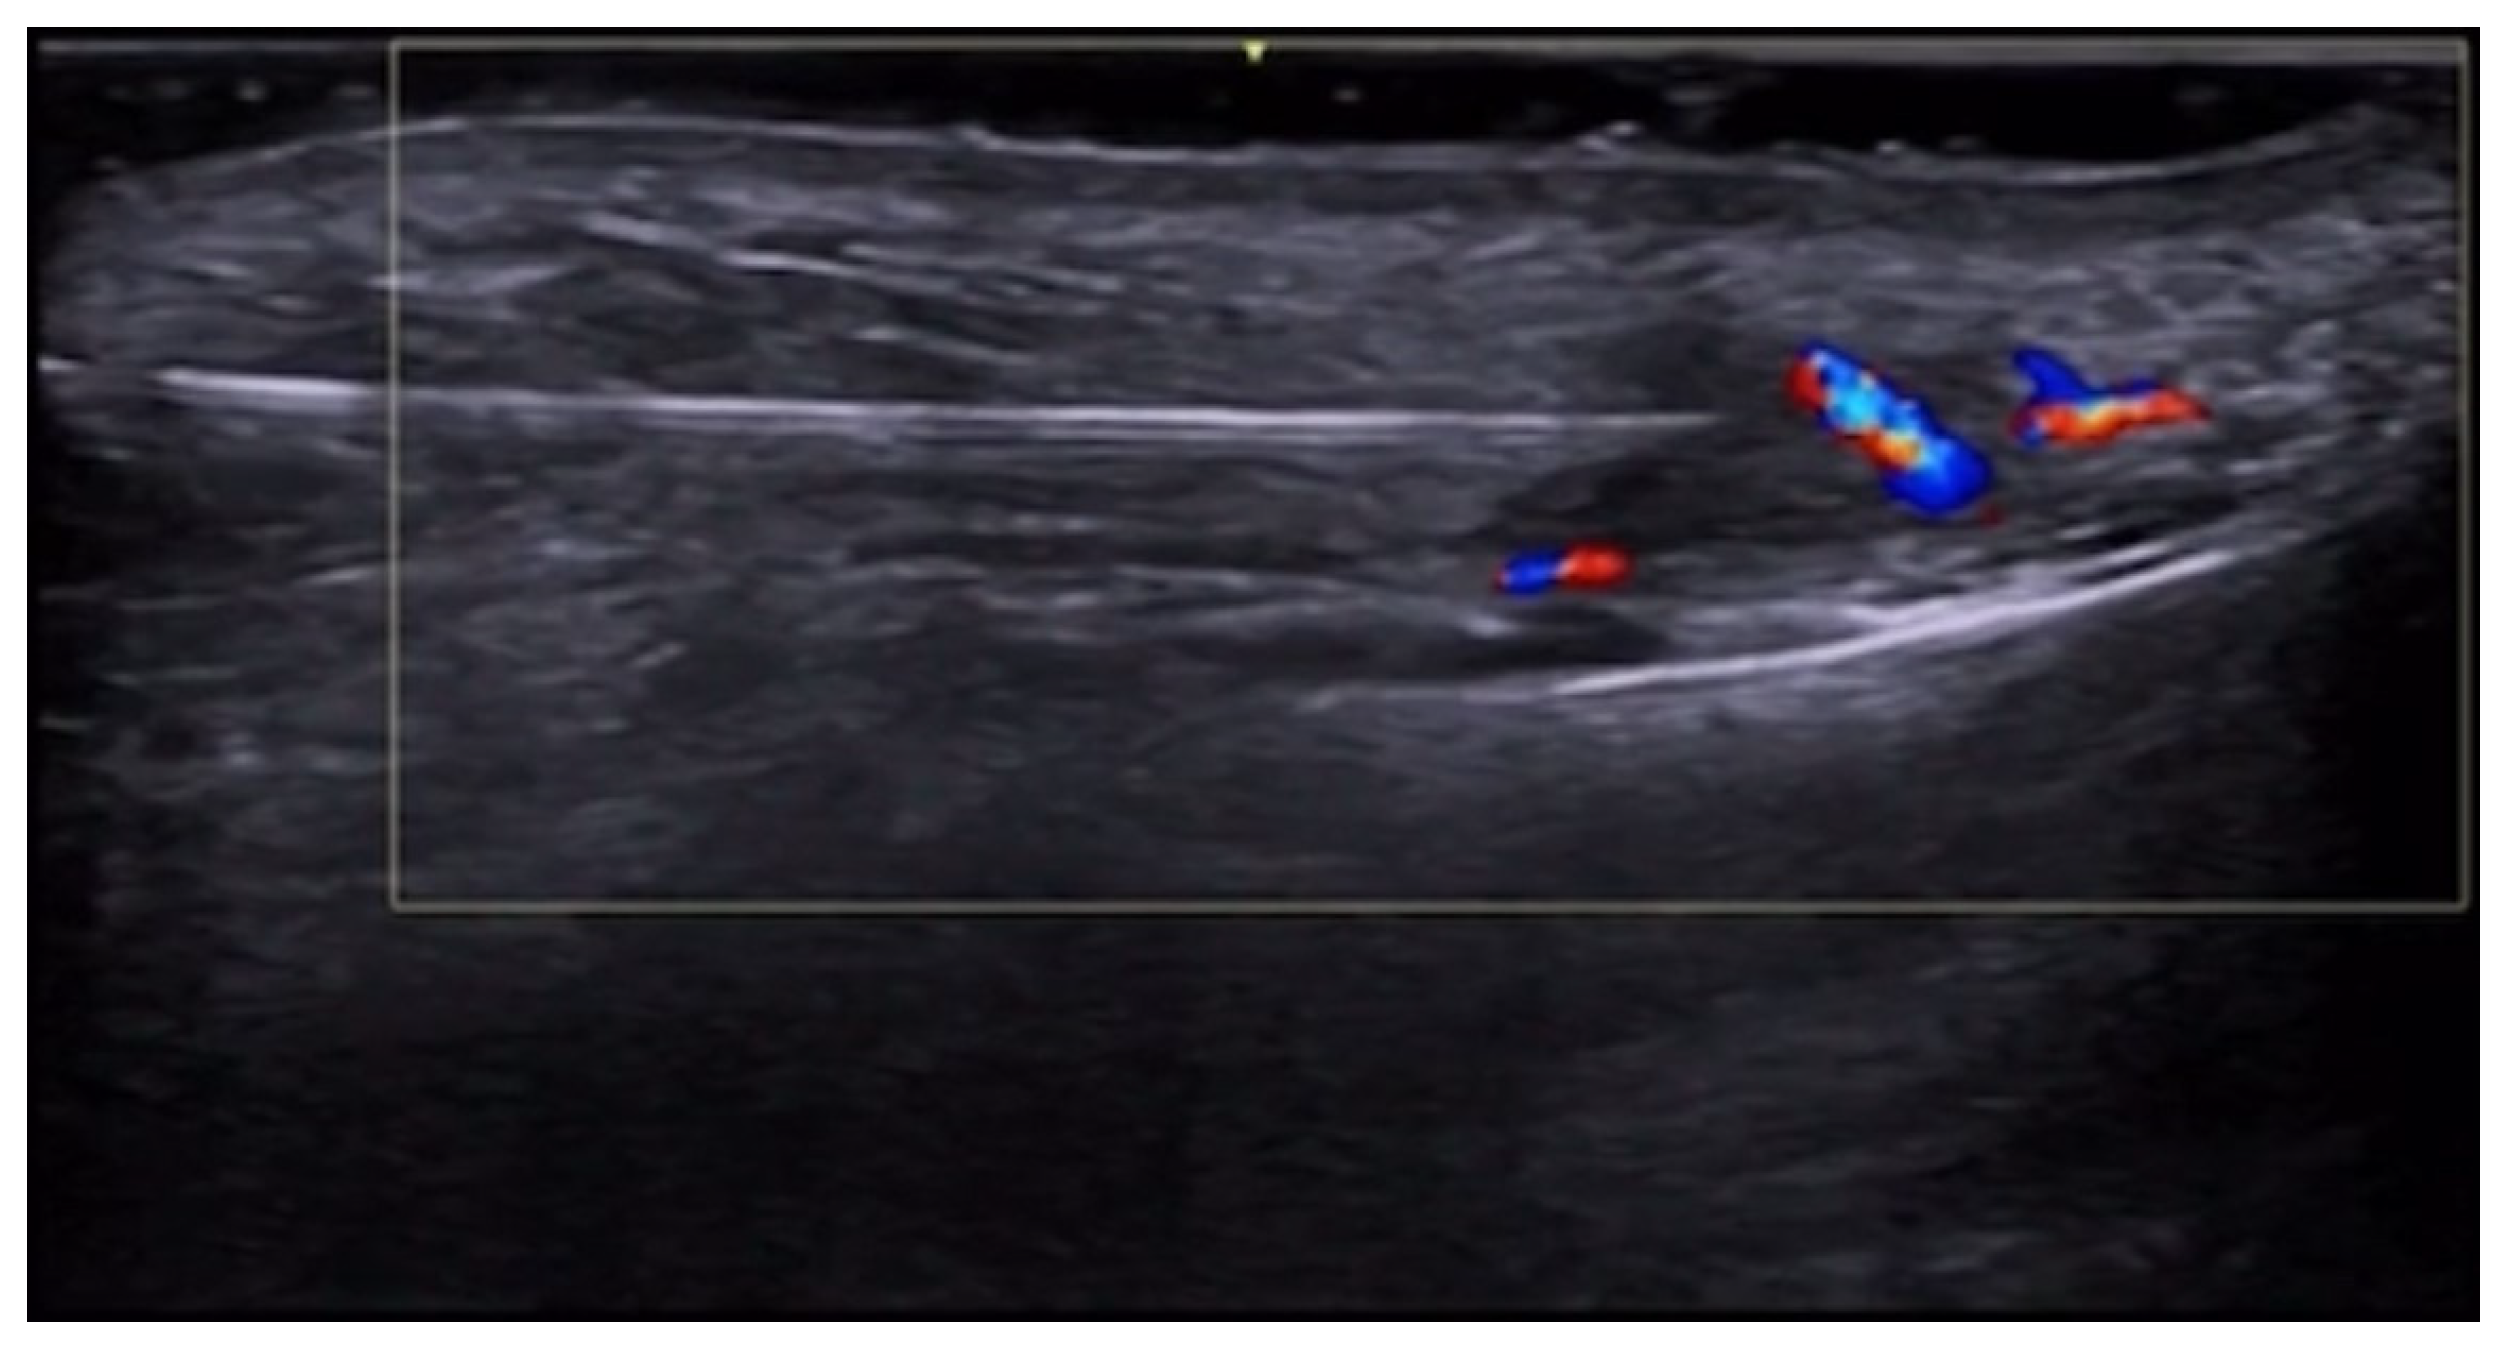

- Velthuis, P.J.; Jansen, O.; Schelke, L.W.; Moon, H.J.; Kadouch, J.; Ascher, B.; Cotofana, S. A Guide to Doppler Ultrasound Analysis of the Face in Cosmetic Medicine. Part 1: Standard Positions. Aesthetic Surg. J. 2021, 41, NP1621–NP1632. [Google Scholar] [CrossRef]

- Vasconcelos-Berg, R.; Izidoro, J.F.; Wenz, F.; Müller, A.; Navarini, A.A.; Sigrist, R.M.S. Doppler Ultrasound-Guided Filler Injections: Useful Tips to Integrate Ultrasound in Daily Practice. Aesthetic Surg. J. 2023, 43, 773–783. [Google Scholar] [CrossRef]